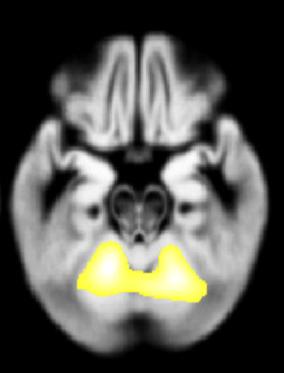

Parkinson's Disease

Areas of research:Parkinson's Disease